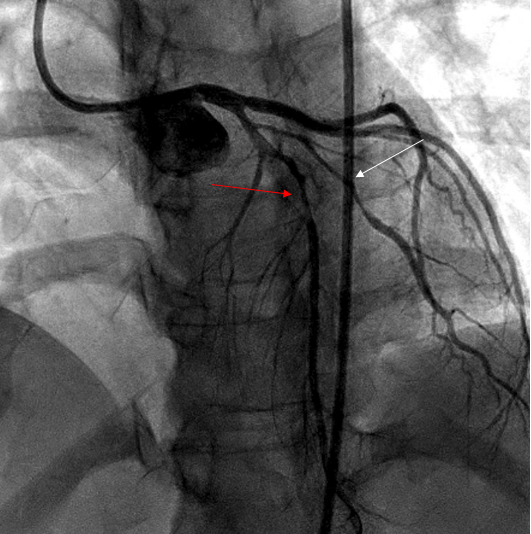

The most common artery involved is distal LAD followed by obtuse marginal. SCAD can be multivessel in 14 % of cases, according to one study [14] (Figure 2).

Figure 2: Coronary angiogram showing type 2 SCAD in LAD (red arrow) and diagonal (white arrow) in 35-year-old women presented with chest pain 3 weeks postpartum.